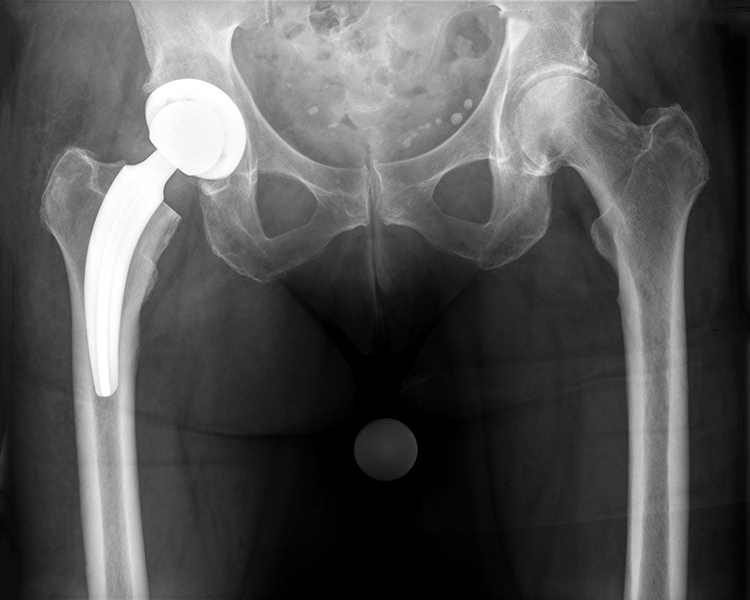

zementfreie Hüftendoprothesen

zementfreie SPCL Schaftprothese mit zementfreier Pfanne (Firma Link)

Hybrid-Hüftendoprothese (zementierter SP II-Schaft mit zementfreier Pfanne, Fa. Link)

Zementierte Hüftendoprothesen und Hybrid-Hüftendoprothesen